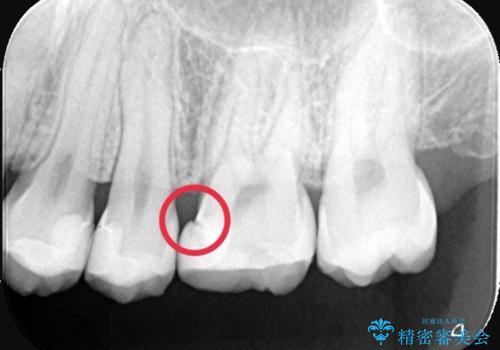

- 主訴:右上6番目の歯が黒ずんで見える。

右上6番に保険適用の歯冠色材料を使ったインレーが入っていましたが、歯質とインレーとの境目に不適部位が存在しそこから二次う蝕になっていました。

セラミックインレーでのやり替えを提案し、また残存歯質量と破折のリスクを説明し、アンレー形態となりました。

おそらくCAD/CAMインレーと思われる補綴物と歯質の不適合による二次う蝕でした。また、インレーを除去したところ、側室底面の歯質の上に裏層材が一部乗っており、歯質マージンとなっていなかったこともリークの一つの原因と考えられます。

適合性、審美性、材料安定性からセラミックインレーでのやり替えとなりました。う蝕を除去いていくと、残存歯質が薄く破折リスクの高い部位が出てきたため患者さんにも説明し、アンレー窩洞としました。